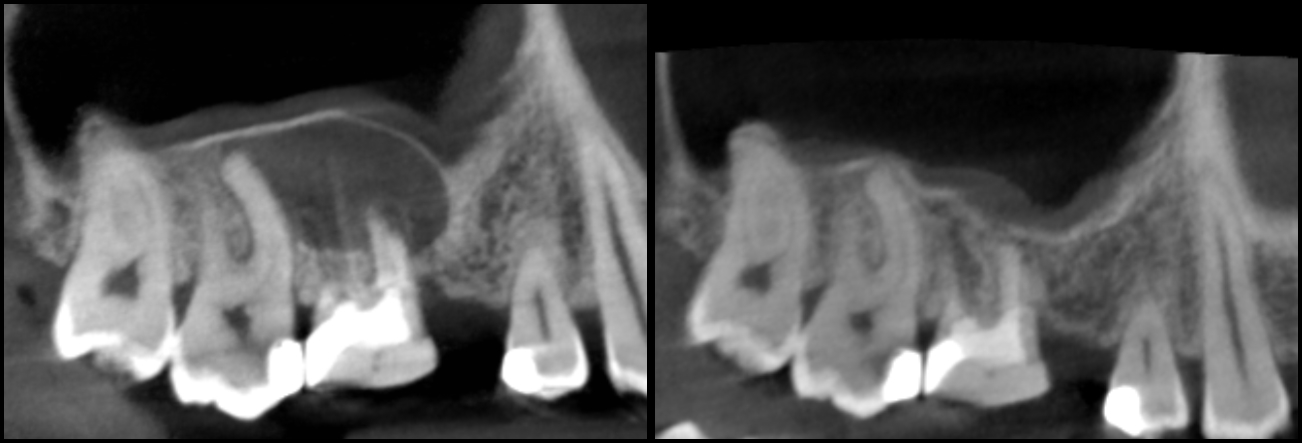

Kanały policzkowe udało się opracować i wypełnić do 1/3 wierzchołkowej, dalsze części kanałów były całkowicie zobliterowane. W trakcie opracowywania kanału podniebiennego zauważono wyciek żółtego opalizującego płynu spoza wierzchołka korzenia zęba, który po kilku minutach samoistnie ustał. Zasugerowało to obecność torbieli korzeniowej. Po zakończeniu leczenia endodontycznego wykonano zdjęcie punktowe kontrole (ryc. 2) oraz tomografię komputerową wiązki stożkowej (cone beam computed tomography – CBCT) opisywanego zęba. Jej rezultat przedstawiają ryciny 3‑6. Widzimy na nich znacznych rozmiarów torbiel korzeniową, która w toku leczenia musi zostać usunięta. Ustalono rozpoznanie ostateczne – torbiel okołowierzchołkowa. Omówiono z pacjentem jego stan i zaproponowano dalsze leczenie, na które wyraził zgodę.

Ryc. 3. CBCT – obraz zmiany w płaszczyźnie strzałkowej.

Ryc. 4. CBCT – obraz zmiany w płaszczyźnie czołowej.